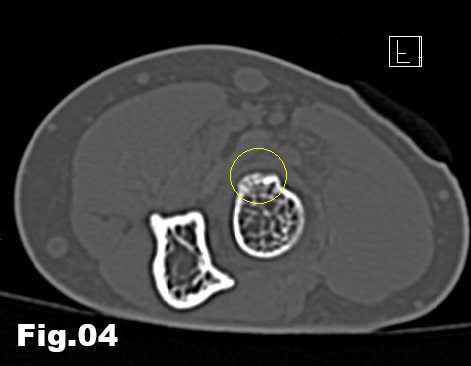

A 51-years-old healthy female, with no history of upper limb injuries, complained of an anterior and proximal left forearm tenderness associated with weakness of the extensor muscles of the forearm. An ultrasound scan was performed and demonstrated a thickened and hypoechoic posterior interosseous nerve (PIN) at the arcade of Frohse, with hypervascularization of the perineurium. In its deeper aspect, there was a subtle irregularity of the radial metaphysis (Fig1,2). The plain film showed a sessile irregularity of the anterior region of the metaphysis (Fig 3). Unenhanced MRI and CT scan were also performed. The CT scan showed the irregularity of the radius (Fig 4) and in the MRI (Fig 5), it was reported as an osteochondroma like metaphyseal lesion of the radius. Initial treatment included a corticosteroid injection around the PIN, but without decrease of symptomatology. The orthopedic surgeon then proceeded with an osteochondroma resection to release the PIN. The upper limb surgical team performed the surgery (Fig 6), and they found a thickened, hyperaemic PIN, adjacent to the osteochondroma (Fig 6,7). They resected the osteochondroma and debrided the PIN (Fig 8). The patient recovered full muscular strength and the tenderness progressively disappeared.

Fig 4: Axial and sagital CT scan views, showing the osteochondroma (circle).